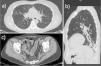

La paciente se encontró asintomática desde el punto de vista respiratorio hasta octubre de 2017, cuando comenzó con tos y expectoración. Se realizó TC de tórax de alta resolución, en la que se describió la presencia de bronquiectasias cilíndricas en lóbulo inferior izquierdo (fig. 1). En cultivos de esputo no se aislaron microorganismos potencialmente patógenos. Desde el punto de vista funcional, la espirometría mostró un patrón obstructivo en grado moderado-grave (FEV1 1,81 L [59%]; FVC 3,09 L [77%]; FEV1/FVC: 0,59). En enero de 2018 fue valorada en la consulta de bronquiectasias: la paciente refirió presentar expectoración purulenta diaria de aproximadamente 40 cc al día y haber precisado 4ciclos de antibiótico desde octubre de 2017. Por ello, se inició tratamiento con solución salina hipertónica al 6% para facilitar la expectoración de secreciones y broncodilatadores inhalados (bromuro de ipratropio y salbutamol). Al mes del inicio de dicho tratamiento (febrero 2018), debido a la persistencia de expectoración purulenta, aunque en menor cuantía que al inicio del uso de la solución salina hipertónica, se añadió ampicilina nebulizada con el objetivo de mantener a la paciente sin exacerbaciones.

a) Corte axial de TC en ventana pulmonar en el que se aprecian opacidades micronodulillares con distribución en «árbol en brote» en el segmento lateral del lóbulo medio, compatibles con afectación infecciosa de la vía aérea. b) Reconstrucción sagital de TC en ventana pulmonar que muestra una opacidad periférica de aspecto infeccioso en el LII asociada a bronquiectasias. c) Corte axial de TC de pelvis con contraste en ventana de partes blandas, en el que se visualiza engrosamiento y edema submucoso de aspecto crónico de las paredes del colon sigmoide, en relación con la manifestación inflamatoria intestinal de la paciente.